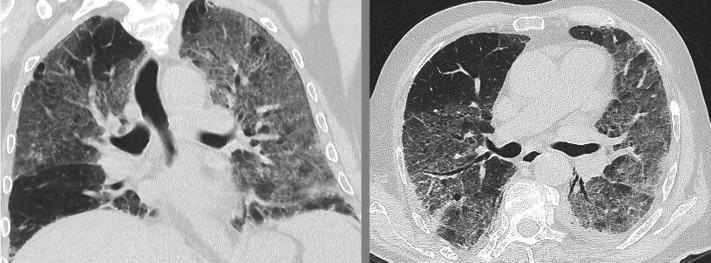

两例免疫功能低下患者并发弥漫性肺泡出血,为严重新型冠状病毒病 2019 的并发症。

Two Immunocompromised Patients With Diffuse Alveolar Hemorrhage as a Complication of Severe Coronavirus Disease 2019.

Diffuse alveolar hemorrhage (DAH) is a severe and potentially life-threatening disease manifestation. In addition to autoimmune diseases such as antineutrophil cytoplasmic antibody-associated vasculitis and anti-glomerular basement membrane syndrome, pulmonary viral infections are known to be culprits of DAH. Health-care providers worldwide in the coronavirus disease 2019 pandemic have been confronted with an unprecedented number of viral lung infections, with great variance in symptoms and severity. Hemoptysis, the key symptom of DAH, is a rare complication. We present two cases of immunocompromised patients with rapidly developing hypoxemic respiratory failure and evidence of DAH in the context of severe acute respiratory syndrome coronavirus 2 infection.

摘要

弥漫性肺泡出血 (DAH) 是一种严重且可能危及生命的疾病表现。除了抗中性粒细胞胞质抗体相关性血管炎和抗肾小球基底膜综合征等自身免疫性疾病外,肺病毒感染也已知是 DAH 的罪魁祸首。在 2019 年冠状病毒病大流行期间,全球的医疗保健提供者面临着数量空前的病毒性肺部感染,症状和严重程度差异很大。咯血是 DAH 的关键症状,但较为罕见。我们报告了两例免疫功能低下患者的病例,他们在严重急性呼吸综合征冠状病毒 2 感染的背景下迅速出现低氧血症性呼吸衰竭和 DAH 的证据。